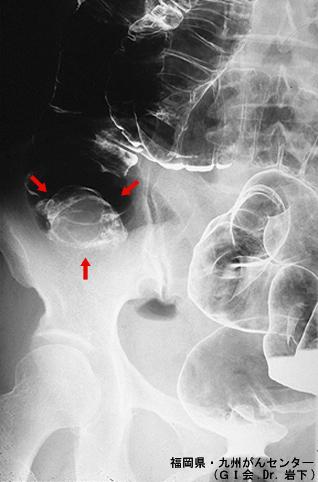

장중적을 초래한 회장의 염증성류 선유용종(IFP)---1980년대의 증례(GI회, Dr.이와시타)---

Fukuoka Pref., 큐슈암센터 (Dr.岩下)

종양양 병변/염증성 유섬유 용종(IFP)

대장/회맹부

X-P

30~34